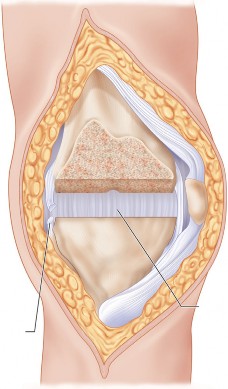

مفصل الركبة هو أحد أكبر وأعقد المفاصل في جسم الإنسان، وهو ضروري للحركة اليومية مثل المشي والجري والقفز والانحناء. يتكون هذا المفصل من التقاء ثلاث عظام رئيسية:

- عظم الفخذ (Femur): وهو العظم الأطول في الجسم، يشكل الجزء العلوي من المفصل.

- عظم الساق (Tibia): وهو العظم الرئيسي في الجزء السفلي من الساق، يشكل الجزء السفلي من المفصل.

- الرضفة (Patella): وهي عظمة صغيرة مثلثة الشكل، تُعرف أيضًا باسم "صابونة الركبة"، تقع أمام المفصل لحمايته وتسهيل حركة الأوتار.

تُغطى نهايات هذه العظام بغضروف مفصلي أملس ومرن (غضروف زجاجي)، يسمح للعظام بالانزلاق بسلاسة فوق بعضها البعض دون احتكاك، ويمتص الصدمات. يوجد أيضًا غضروفان هلاليان (Menisci) على شكل حرف C بين عظم الفخذ وعظم الساق، يعملان كممتصات صدمات إضافية ويزيدان من استقرار المفصل.

يُحاط المفصل بمحفظة مفصلية تحتوي على سائل زليلي (Synovial Fluid) يغذي الغضروف ويزيت المفصل. تُعزز استقرار الركبة بواسطة شبكة قوية من الأربطة:

- الأربطة الصليبية (Cruciate Ligaments): الأمامي والخلفي، يقعان داخل المفصل ويمنعان الانزلاق الأمامي والخلفي لعظم الساق.

- الأربطة الجانبية (Collateral Ligaments): الإنسي والوحشي، يقعان على جانبي المفصل ويوفران الاستقرار الجانبي.

تعمل العضلات المحيطة بالركبة، مثل العضلة الرباعية في الفخذ وعضلات أوتار الركبة، مع الأوتار على تحريك المفصل وتثبيته. أي خلل في هذه المكونات يمكن أن يؤدي إلى الألم، عدم الاستقرار، وتدهور وظيفة الركبة، وهو ما يحدث غالبًا في حالات خشونة الركبة التقوسية.